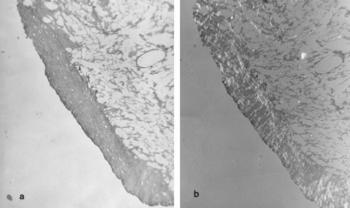

74. ábra. Egyenlőtlen vastagságú, elmeszesedett porcréteg, vaskos corticalis az arthrosisos ugrócsontban (makroszkóposan lásd 73. képen) Pikrosziriusz festés. 100× nagyítás. a) fénymikroszkópos, b) polármikroszkópos felvétel

Másodlagosnak nevezik, amikor valamilyen biomechanikai hiba miatt egy ízületben, vagy egy végtag teherviselő ízületeiben alakul ki az OA. Rendszerint megállapítható a rossz helyzetű törésgyógyulás, esetleg az ízületi tengely megváltozása (X-láb és vagy gacsos térd). A veleszületett csípődysplasiához 20-30. év körül súlyos arthrosis társul. Előfordulhat, hogy a monoton, repetitiv mozgás csak egyetlen vagy a szimmetrikus (könyök) ízületeket terheli, s ilyenkor foglalkozási ártalomnak tekinthető (During és mtsai 1994). A másodlagos forma makroszkópos, mikroszkópos és röntgenmorfológiai képe mindenben megegyezik a primer osteoarthritisével (73. ábra, 74. ábra).